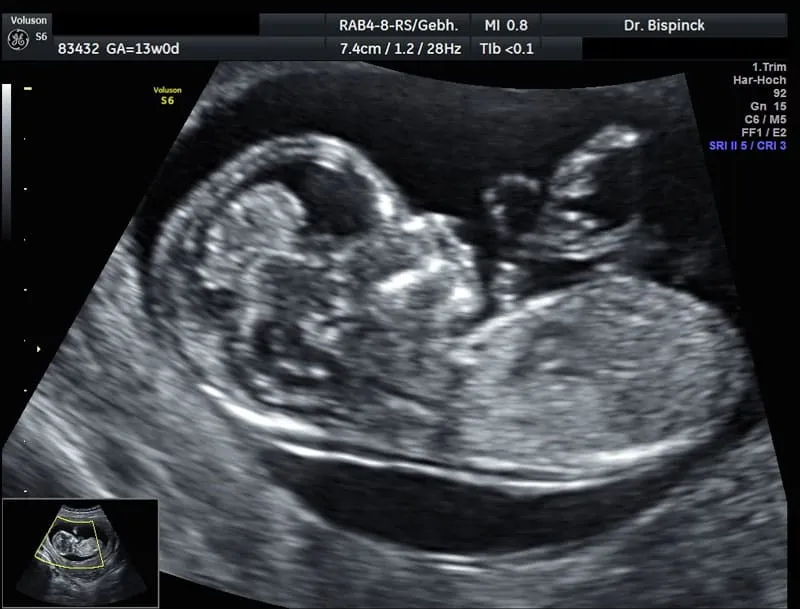

Erst-Trimester-Screening

Aus den Messergebnissen, dem mütterlichen Alter und dem Schwangerschaftsalter wird dann ein statistisches individuelles Risiko für das Auftreten einer Trisomie 21 oder 13 und 18 errechnet. Weitere Gründe für eine verbreiterte Nackenfalte können auch kindliche Herzfehler, Zwerchfell-/Nabelbruch, Skelett- oder Stoffwechseldefekte sein. Mitunter liegt kein besonderer Grund vor und der weitere Schwangerschaftsverlauf ist unkompliziert.

Viele Paare nutzen diese Untersuchung, um bei einem ggf. durch das mütterliche Alter (ab 35. Lj) statistisch erhöhten Risiko für eine Chromosomenstörung auf eine Fruchtwasserpunktion zu verzichten.